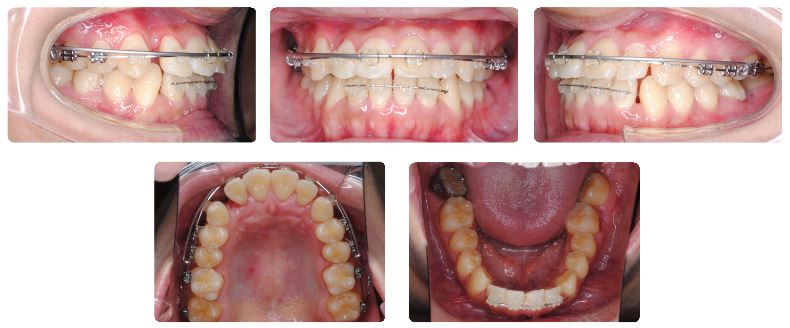

カリエールモーションを外してマルチブラケット装置を装着した直後の状態です。

下顎にマルチブラケット装置を装着後4か月後の状態です。

現在ゴムメタルという素材のワイヤーで治療継続中です。